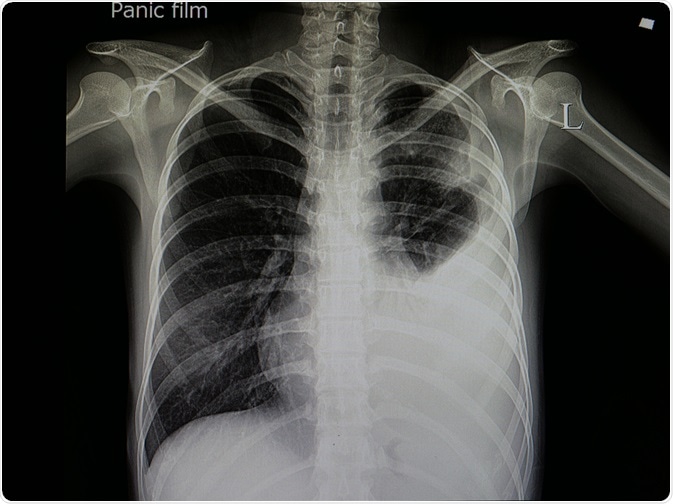

If pneumonia is suspected, a physician may ask for additional tests, including chest x-ray, chest CT scan, complete blood count, blood culture, swab test, open lung biopsy, sputum culture, and blood gas test.

An X-ray or CT scan of the chest is usually done to visualize the location and severity of the inflammation in the lungs. In a chest x-ray, certain characteristics that can be used to differentially diagnose viral pneumonia include interstitial infiltrates, bilateral infiltrates, and patchy distribution of interstitial infiltrates. Moreover, thin-section thoracic CT is particularly important for detecting specific features of viral pneumonia.

Chest X-Ray

Image Credit: create jobs 51/Shutterstock.com